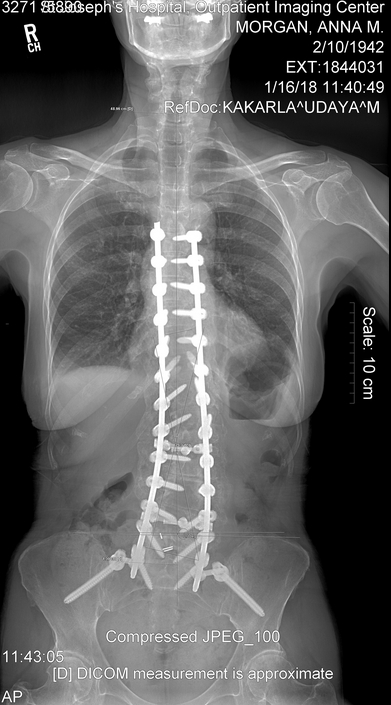

I go January 16 to have my year X-ray and be checked. If everything is healing correctly and the hardware is holding, I will accept this as my new normal.

My year is up and I have had my 1 year x-rays and Surgeon appointment. Everything looks to be holding. I guess you would say that I no longer have scoliosis. I do still have that cardboard feeling in the muscles of my back. I mentioned to Dr. Kakarla that when I try to lift a gallon of milk the back goes into spasms and gets tighter. He decided that I needed another 30 sessions at physical therapy to make my upper body and legs stronger.

I still am doing the 4 mile hike. So with 3 times a week at PT and the hike my days are busy. Hope we can get started with our summer by Easter. Here are two views of my spine at my one year checkup.

The x-rays for the 5 year checkup show that everything is holding just fine. I was ready to have them make sure that the rods and screws were still doing okay. Remember those of us that have had this much surgery, find that doctors, family and people around us have a hard time remembering that we cannot do what others can. I carry my pictures of the x-rays in my phone.

Here are my January 2022 x-rays